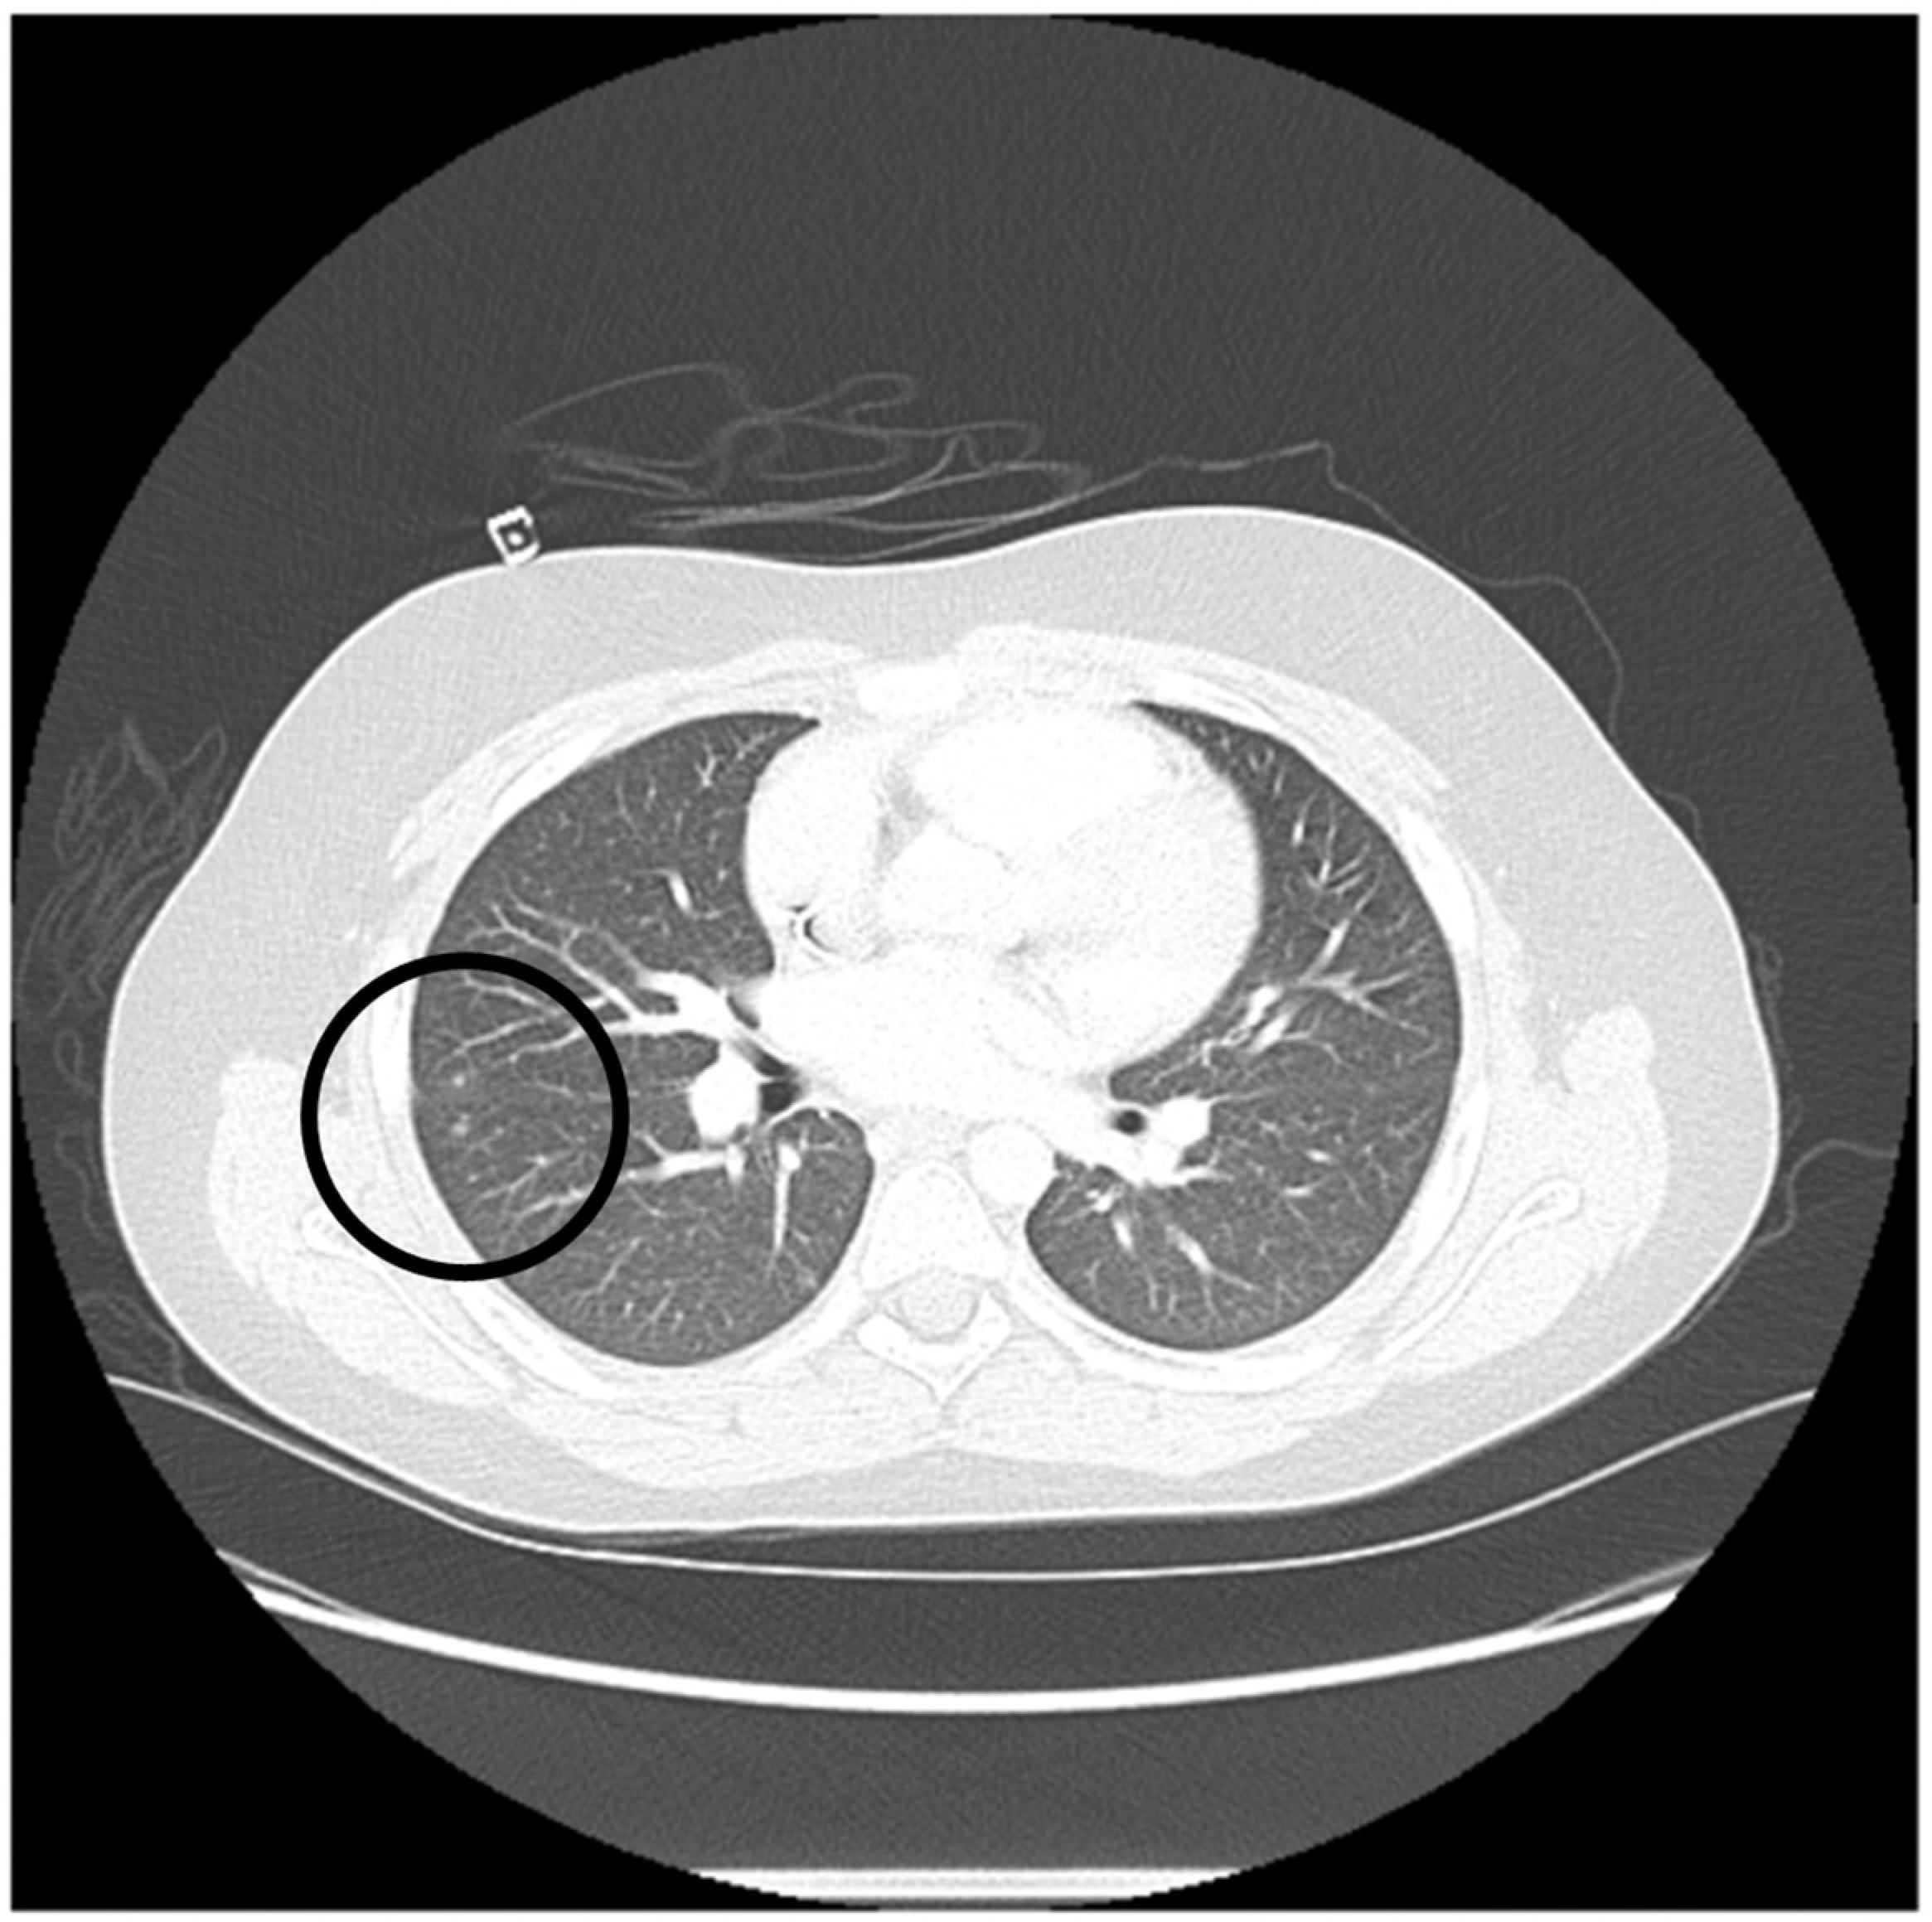

| 3 | 6/F | Very high risk acute myeloid leukemia with t(6;9) (p23;q34) and DEK/NUP214 fusion and FLT3-ITD positive (allelic ratio 0.75) | CR1 | Invasive pulmonary aspergillus infection requiring triple anti-fungal therapy (Voriconazole, liposomal amphotericin and caspofungin) SARS-CoV-2 infection treated with remdesivir | PBSC/MUD | 10/10 | TNC: 14.6 × 108/kg CD34+: 7.6 × 106/kg | F/M | O+/O+ | +/+ | IV PTCy 50 mg/kg on day +3 and +4 followed by MMF and tacrolimus starting day +5 | +16/+31 | +183 |